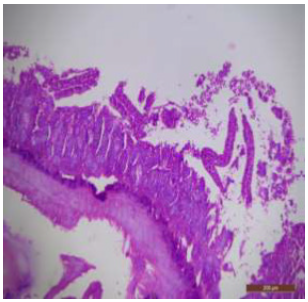

The ileal mucosa of control rat was built up of numerous folds forming the villi, through which connective tissue of the lamina propria containing tubular glands i.e., crypts of Leiberkühn were present (Figure 18). The epithelial lining of the villi was composed of Paneth cells and intestinal glands (Figure 19). In fluorotic rats, there were abnormal shaped, damaged and broken villi with bulbous tips. Lymphatic dilation and haemorrhaged in lamina propria were also seen (Figure 20). In the ileal mucosa, prominent inflammation, distortion of crypts with shredded cells inside the crypts were visible (Figure 21). Swollen and necrotic crypts were present (Figure 22). The ileal tissue showed disruptions in the normal mucosal architecture with signs of villous atrophy and cell infiltration (Figure 23). Lymphatic infiltration was prominent and numerous enlarged lymph nodules appeared in lamina propria of villi. There were ill-defined cell boundaries, vacuolated cytoplasm and pyknotic nuclei (Figure 24).

Figure 17: T.S. of ileum of control rat showing scattered and broken villi (↑) and decrease in size of intestinal glands (↑). H&E × 100.

Figure 18: T.S. of ileum of control rat showing mucosa (↑), submucosa (↑), muscularis externa (↑) and serosa (↑). H&E × 100.

Figure 19: T.S. of ileum of control rat showing normal villi epithelial lining, crypts of Leiberkuhn (↑) and submucosa. Below the villi, the intestinal glands (↑) are present. H&E × 100.